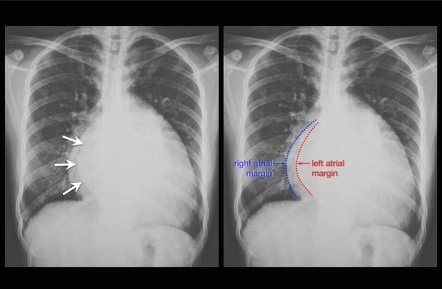

Identify appropriate investigations for mitral stenosis